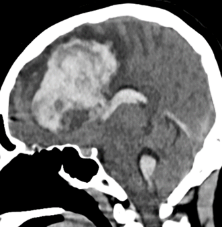

▲经过给患者“量身定制”的介入栓塞术治疗后,畸形血管团完全消失,正常的脑动脉及分支保留通畅

乘胜追击,刻不容缓!征得家属同意后,冯大勤立即带领神经外科脑血管病专业团队,在麻醉科、放射学科介入手术室等团队密切配合下,有条不紊地给叶女士完成了“全脑血管造影术”“球囊辅助下脑动静脉畸形栓塞术”和“支架辅助血管重建术”,在保留病灶周围正常血管结构的前提下成功栓塞了畸形血管团。手术一气呵成,体现了微创、高效、安全和个性化的理念与特点。术后经麻醉复苏,患者意识也恢复如初。